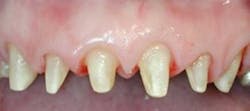

Optimal soft-tissue healing around provisional restorations on teethWhen it comes to implant provisionalization and final restorations, I prefer screw-retained restorations. This does require that implant placement is such that access is through the central fossa of posterior teeth and the cingulum of anterior teeth. Anything near the incisal edge will require either an angulated abutment or a cementable restoration. It’s true that screw-retained restorations do require a little more patience, but it will pay off in spades once you do a few.Here are a few easy steps to make a screw-retained implant provisional restoration that will set the stage for your final crown. This can be done in the mouth for immediate loading situations or after implant uncovering. These techniques can also be done on the bench top after an implant level impression and then delivered to the mouth.1. Place the screw-retained implant cylinder on the implant using the abutment screw.

10. After one to two weeks of tissue healing around the polished provisional, the tissue is shaped and ready for impressions and final restoration.

11. Final restoration in place with well-developed emergence profile and tissue contours.